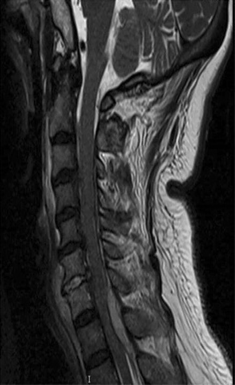

MRI

- Bone marrow edema in infected vertebrae, discs and paraspinal soft tissues

- Dark on T1 and bright on T2 images

- Enhancement of inflamed tissues after contrast

Spinal epidural abscess, osteomyelitis, and discitis MRI cervical spine (T2-weighted; sagittal plane) High signal intensity collections are seen in the posterior epidural space. The largest collection causes anterior displacement and compression of the spinal cord from C7-T2. The appearance is consistent with epidural abscess. High signal intensity consistent with osteomyelitis and discitis involves the C6 and C7